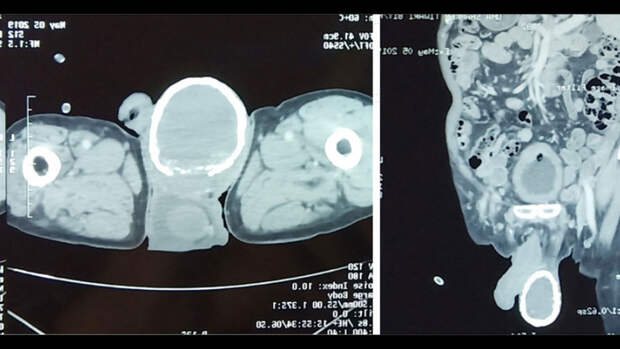

О необычном случае врачи рассказали в статье в журнале BMJ.80-летний пациент, обнаружив у себя в моче кровь, поспешил обратиться к врачам. На осмотре те обнаружили еще одну проблему - правое яичко мужчины увеличилось в несколько раз и было твердым как камень. Компьютерная томография показала: у мужчины водянка яичка (гидроцеле). При этом заболевании между оболочками яичек скапливается серозная жидкость. Гидроцеле может быть как врожденным, так и приобретенным, во втором случае оно возникает в результате травм, операций на половых органах, воспалительных заболеваний яичка. Как правило, приобретенная водянка проходит по мере лечения основного заболевания. Возможно и оперативное лечение.

Однако при водянке мошонка остается мягкой, а у пациента она была твердой.

Как оказалось, причина этого - толстый слой кальция, сформировавший внутри своеобразную "скорлупу".

Кальцификация, отложения солей кальция - само по себе нередкое явление. Ее причиной могут стать травмы, операции, почечная недостаточность. В данном случае ее спровоцировала водянка, считают врачи. С таким проявлением кальцификации они столкнулись впервые - впервые подобное отложение кальция было описано в 1935 году и с тех пор известно лишь о нескольких подобных случаях.